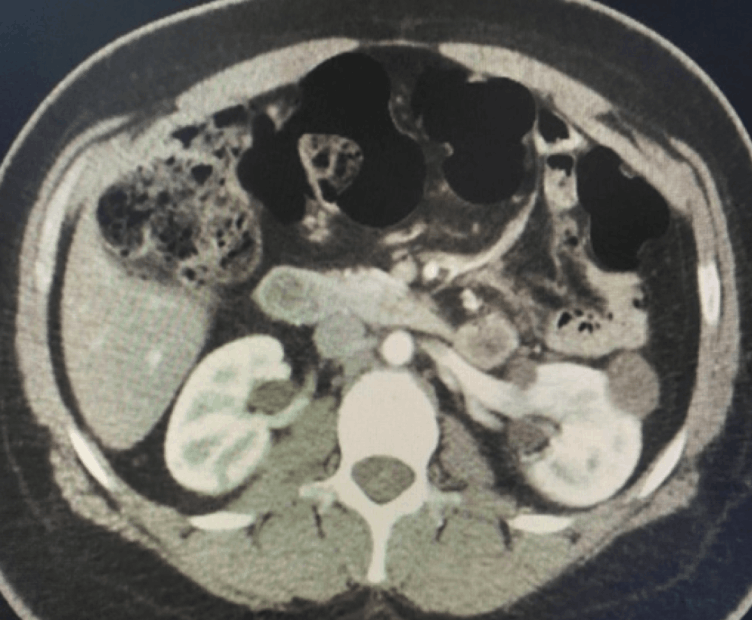

Cerebellar Hemangioblastoma in A Patient With Von Hippel-Lindau Syndrome.

Por Dr. Chrystiano Fonseca Cardoso.

Von Hippel-Lindau syndrome (VHL) is a rare, autosomal dominant genetic disorder with a prevalence of 1 in 36,000. It is characterized by cysts and/or benign tumors in multiple organs with potential for malignant transformation. The main findings are: hemangioblastomas located in the retina and central nervous system (CNS), cysts or solid tumors in various sites (pancreas, liver, kidneys, lymphatic tissue), and pheochromocytoma [1-2].

Diagnosis is made in the presence of some of the classic tumors in individuals with a family history or in the presence of two tumors in those without a family history. Treatment and prognosis vary depending on the alterations presented [3-4].